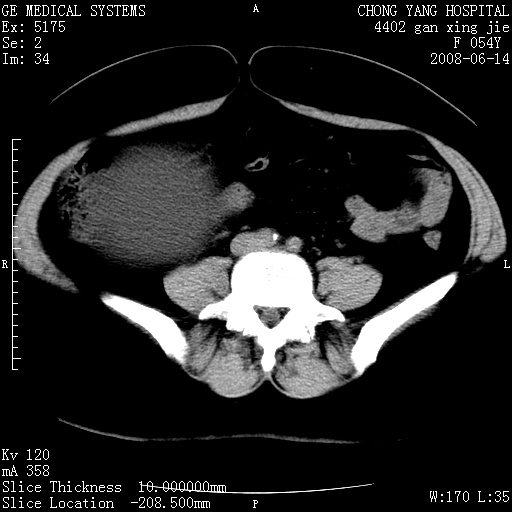

标题: CT14033:F54Y,来源哪? 外伤发现,自述既往无不适。 [打印本页]

标题: CT14033:F54Y,来源哪? 外伤发现,自述既往无不适。

1、脂肪肝。2、腹腔囊性占位,首考虑来源于右肾下极,其次考虑来源于肠系膜。

考虑肠系膜囊肿,脂肪肝

肠囊肿可能性大,与十二直肠水平部呈喇叭口,来源于十二直肠,不排除胰头假囊肿.

1、脂肪肝。2、腹腔囊性占位,首考虑肠源性囊肿或中肾管囊肿。

脂肪肝,来源于腹膜后囊肿可能性大。

脂肪肝,巨大肾囊肿

支持考虑肠系膜囊肿,脂肪肝.

考虑肠系膜囊肿

1)脂肪肝。2)右肾下极巨大囊肿。

右肾下极巨大囊肿可能性大。

右中下腹部囊性肿块,与右肾下极关系密切,考虑右肾下极巨大外生性囊肿;脂肪肝。